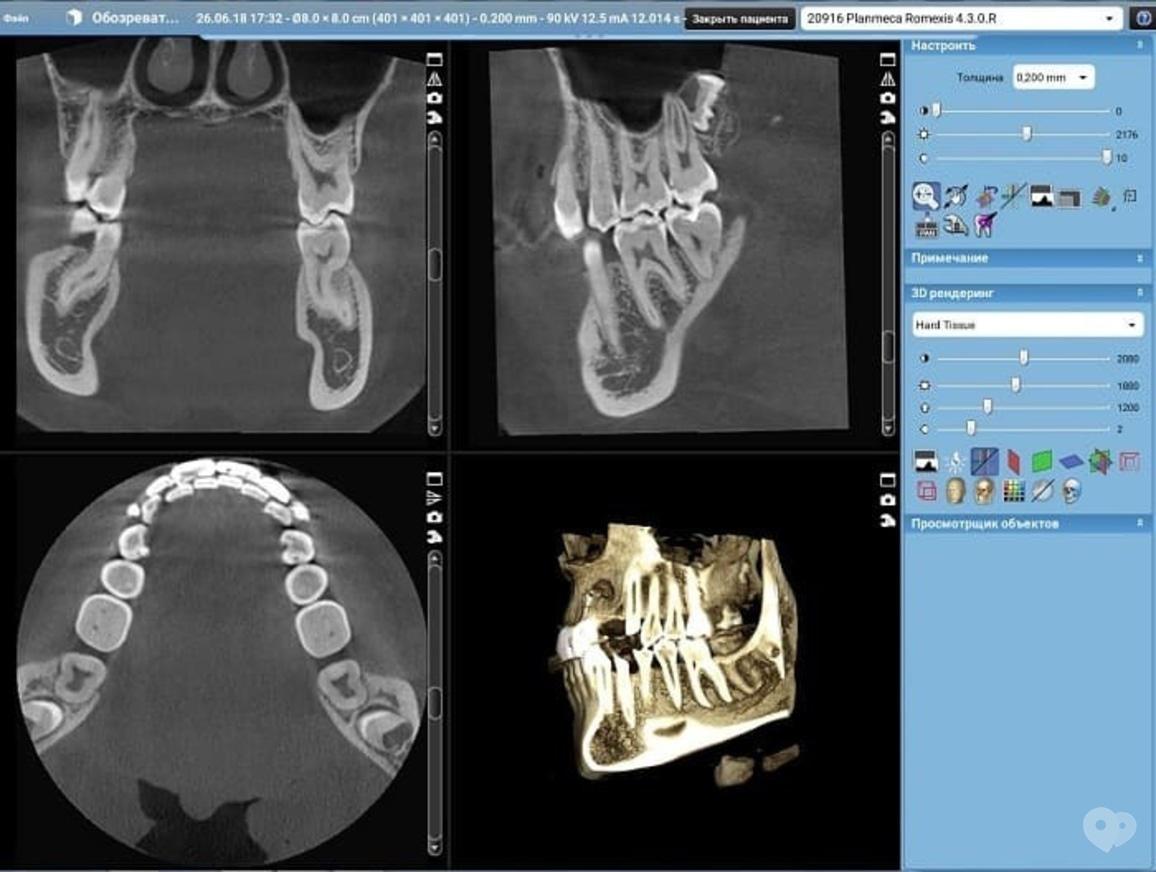

Кт зуба рядом

Кт зуба рядом 109 фотографий